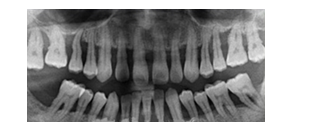

患者女性,59歲,右側(cè)后牙咀嚼無(wú)力,刷牙時(shí)牙齦出血。無(wú)系統(tǒng)性疾病。口腔檢查顯示全口多數(shù)牙牙石(++),牙齦紅腫,探診出血,牙周袋袋深4~6mm,右下后牙有Ⅰ~Ⅱ度松動(dòng),X線片如圖所示:

【答案解析】根據(jù)患者臨床表現(xiàn)和X線片檢查,可明確診斷為慢性牙周炎。